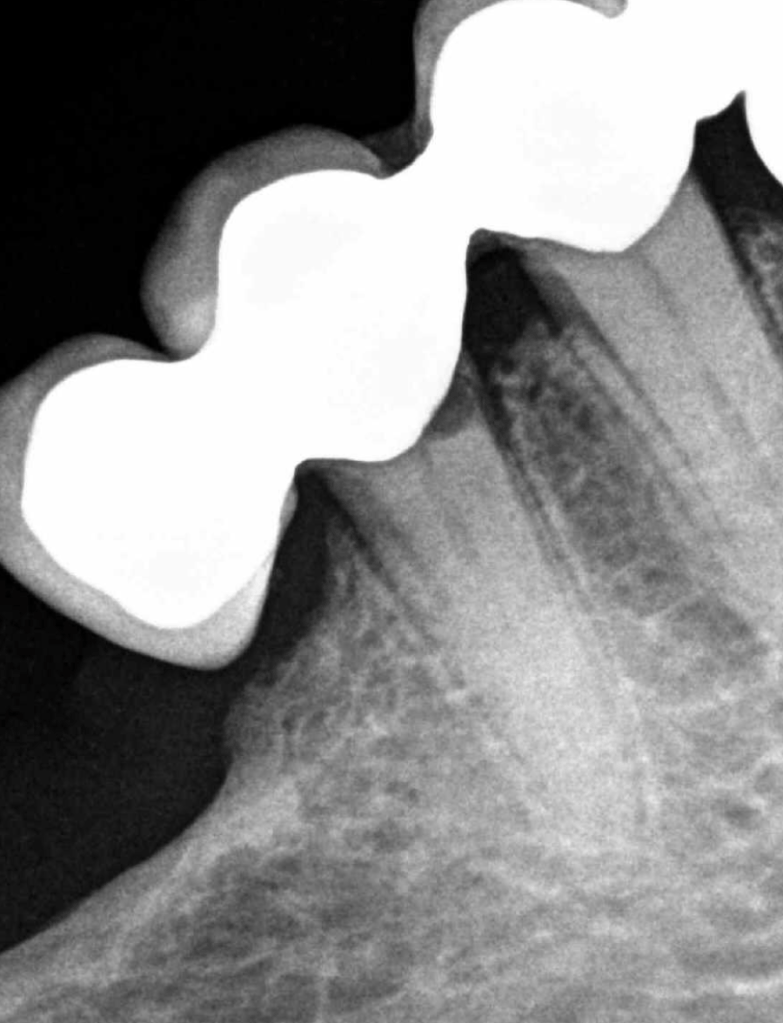

Incisivo superior Endo-perio

Incisivo superior trauma